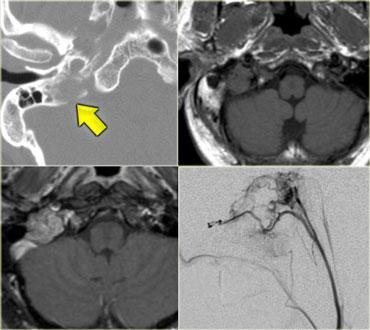

Hình bên trái là một ví dụ về u cận hạch (Paraganglioma) nền sọ.

Hình bên trái là hình ảnh CT của bệnh nhân nam 58 tuổi với biểu hiện đau và tê mặt bên phải khởi phát từ từ, kèm theo nhìn đôi mới xuất hiện gần đây.

Hãy phân tích hình ảnh trước, sau đó tiếp tục.

Có một khối ngấm thuốc nằm phía trước nền sọ và trong vùng xoang hang bên phải.

Trên cửa sổ xương, có hình ảnh xơ cứng nền sọ, đặc biệt ở vùng xương nền (clivus).

Tiếp tục xem hình ảnh MRI.

Hình bên trái là chuỗi xung T1W mặt phẳng đứng dọc và đứng ngang có tiêm thuốc tương phản từ.

Dấu hiệu nổi bật nhất là xương nền (clivus) giảm tín hiệu (màu đen) do xơ cứng.

Xương nền bình thường có tín hiệu cao trên chuỗi xung T1W do tủy xương chứa mỡ.

Có một khối ngấm thuốc nằm phía trước xương nền.

Trên hình mặt phẳng đứng ngang, chúng ta thấy sự ngấm thuốc lan qua lỗ bầu dục (foramen ovale) đến xoang hang bên phải.

Chẩn đoán là ung thư biểu mô tế bào vảy vòm họng (nasopharyngeal squamous cell carcinoma) với xâm lấn nội sọ.

Chẩn đoán phân biệt bao gồm: di căn nền sọ, u lympho, nhiễm trùng mạn tính và thậm chí u màng não (meningioma) – mặc dù đây sẽ là một hình thức lan rộng bất thường của u màng não.